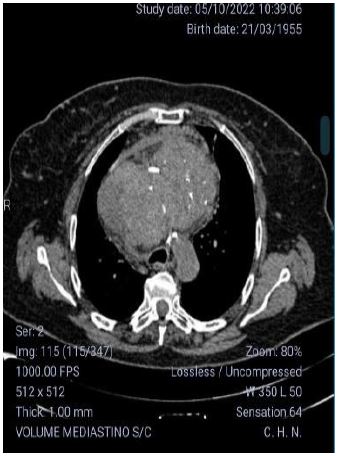

A 68-year-old female patient, smoker since the age of eight, diagnosed with giant diving goiter, irregularly monitored by several endocrinologists in recent years, presenting progressive dyspnea mainly in the supine position. Computed tomography performed on the 10th of may of 2022 revealed a heterogeneous mass with hypodense areas and foci of calcification, measuring 20.6 x 7.5 x 10.7 cm, located in the anterior mediastinum, determining significant compression of the trachea, esophagus and lung parenchyma in correspondence, associated with collateral circulation in the anterior mediastinum and anterior chest wall (Figure 1). Due to the exuberance of the respiratory symptoms that compromised the quality of life, the patient was submitted to complete resection of the diving goiter through cervicotomy associated with sternotomy. Involvement of the innominate trunk was observed, requiring its respective ligation (Figure 2 and 3). The specimen sent for anatomopathological study measured 24 x 13 x 06 cm (Figure 4), weighed 772 g and revealed nodular follicular thyroid disease, with extensive areas of hyalinization.

Figure 1: